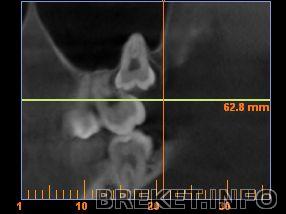

Верхняя была частично выросшей, частично - вросшей в семерку. И корень в гайморовой пазухе...

На семерках были надкусочные пломбы, которые постеменно спиливались... "тянулись" они дугой, никаких кнопок и имплантов... Но у меня в принципе довольно поддатливые зубы + у семерки верхней одного корня нема из-за восьмерки (снимок выше в комментах есть), может за счет этого она тоже более подвижна... Ну и вот внизу щас восьмерку удалили - семерка тоже подвижной была... Ох, я уже и не помню, что начиналось всё с клыков...